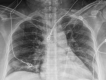

The worldwide incidence of coronavirus disease 2019 (COVID-19) infection is rapidly increasing, but there exists limited information on coronavirus disease 2019 in pregnancy. Here, we present our experience with 7 confirmed cases of coronavirus disease 2019 in pregnancy presenting to a single large New York City tertiary care hospital. Of the 7 patients, 5 presented with symptoms of coronavirus disease 2019, including cough, myalgias, fevers, chest pain, and headache. Of the 7 patients, 4 were admitted to the hospital, including 2 who required supportive care with intravenous hydration. Of note, the other 2 admitted patients who were asymptomatic on admission to the hospital, presenting instead for obstetrically indicated labor inductions, became symptomatic after delivery, each requiring intensive care unit admission.